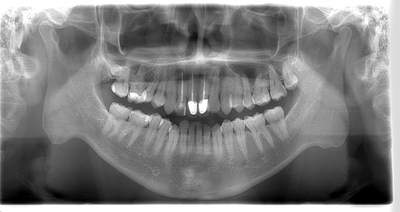

CT

- Before

- After

CTで親知らずと神経(下歯槽管)の位置を確認しました。

親知らずと神経は一定の距離があり、麻痺などのリスクがほとんどないと判断できます。

口腔内

半埋伏の親知らずでした。3糸縫合しました。